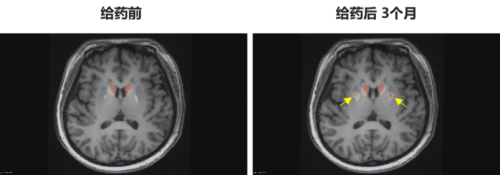

多巴胺能功能成像:神经突触多巴胺能显像是评估人脑黑质纹状体神经元完整性和功能的“金标准”,常用于帕金森病亚临床诊断1-2。接受移植手术3个月后PET-DAT/MRI融合影像明确显示,移植细胞已在患者脑内定植并成功转化为有功能的多巴胺能神经元,双侧纹状体形成显著的de novo新生多巴胺能活性成像(如下图箭头所指), 为功能性治愈提供了最直观的证据。

EOPD患者PET-DAT/MRI融合图像术前与术后三个月对比

注:影像图中黄色箭头指示为NCR201移植后,双侧纹状体出现的新生多巴胺能活性信号,提示移植细胞已定植并高效转化为功能性多巴胺能神经元